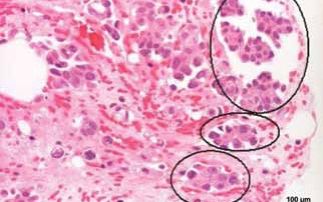

Over the last few years, IR absorption spectroscopy has grown up as a potential analytical method in tissue and cell studies for cancer diagnosis. ...